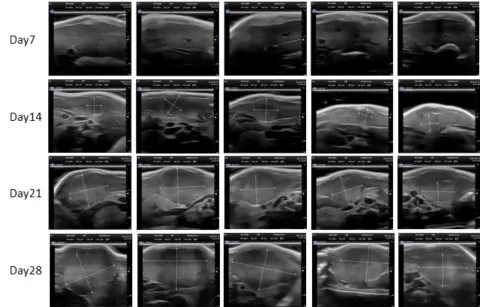

部分beats365PDX原位模型展示

部分beats365PDX原位模型展示